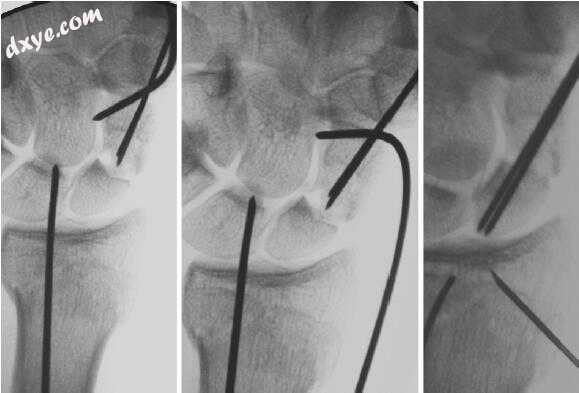

20.jpg

图.20  一旦骨折复位一直使用操纵杆来完成,在远端舟骨片段的中心轴导丝从掌背,捕捉和保持骨折复位。非常不稳定的骨折可能需要两个中心轴线来抵抗弯曲和骨折旋转。